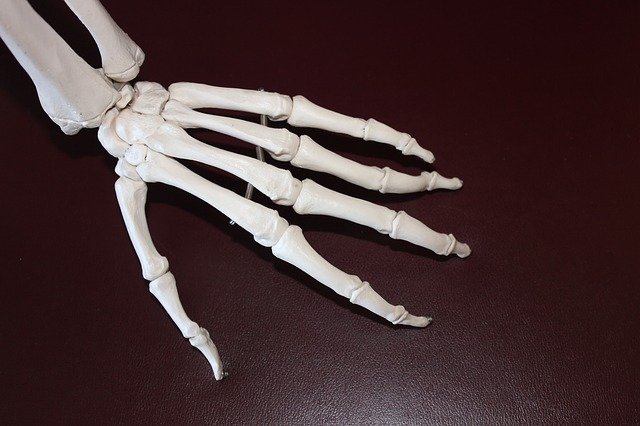

류마티스 관절염 초기 증상 두 번째는 관절이 부어오르는 것으로 염증으로 인해서 관절에 물이차 오르며 점차 부어오르게 됩니다. 만약 방치할 경우 손가락에 기형이 올 수 있으니 병원을 방문해서 치료하는 것이 좋습니다.